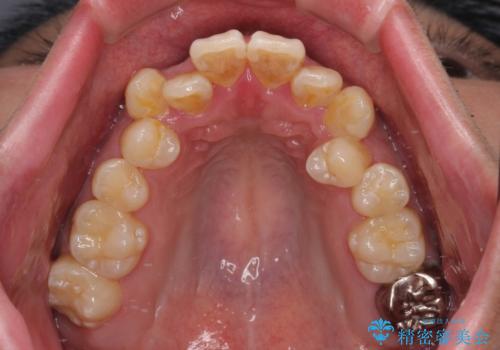

- 「歯並び全体のデコボコをきれいに整えたい」とのご希望で、20代男性の患者様が来院されました。

特に前歯部の叢生(歯の重なり)が強く、見た目だけでなく歯磨きのしにくさも気にされていました。

診査の結果、上下前歯に強い叢生が認められ、歯をきれいに並べるためのスペースが明らかに不足していました。

無理に歯を並べると、前歯が前方に突出するため、抜歯によるスペース確保が必要と判断しました。